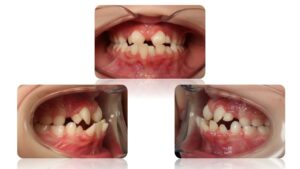

La Classe II Subdivision

La classes II subdivision fonctionnelle est la conséquence d’une mastication préférentielle voir exclusivement unilatérale. Cette dysfonction engendre alors une bascule du plan d’occlusion dans le plan frontal mais également dans le plan vertical et sagittal.

L’orthodontie systémique permet d’appréhender cette pathologie par l’analyse des latéralités mandibulaires (AFMP).

Le traitement qui en découle est donc fonctionnel et stable car il permet une réorientation du plan occlusal, symétrisant ainsi les AFMP et donc la mastication.

C’est donc la fonction qui joue le rôle de contention des traitements systémiques.